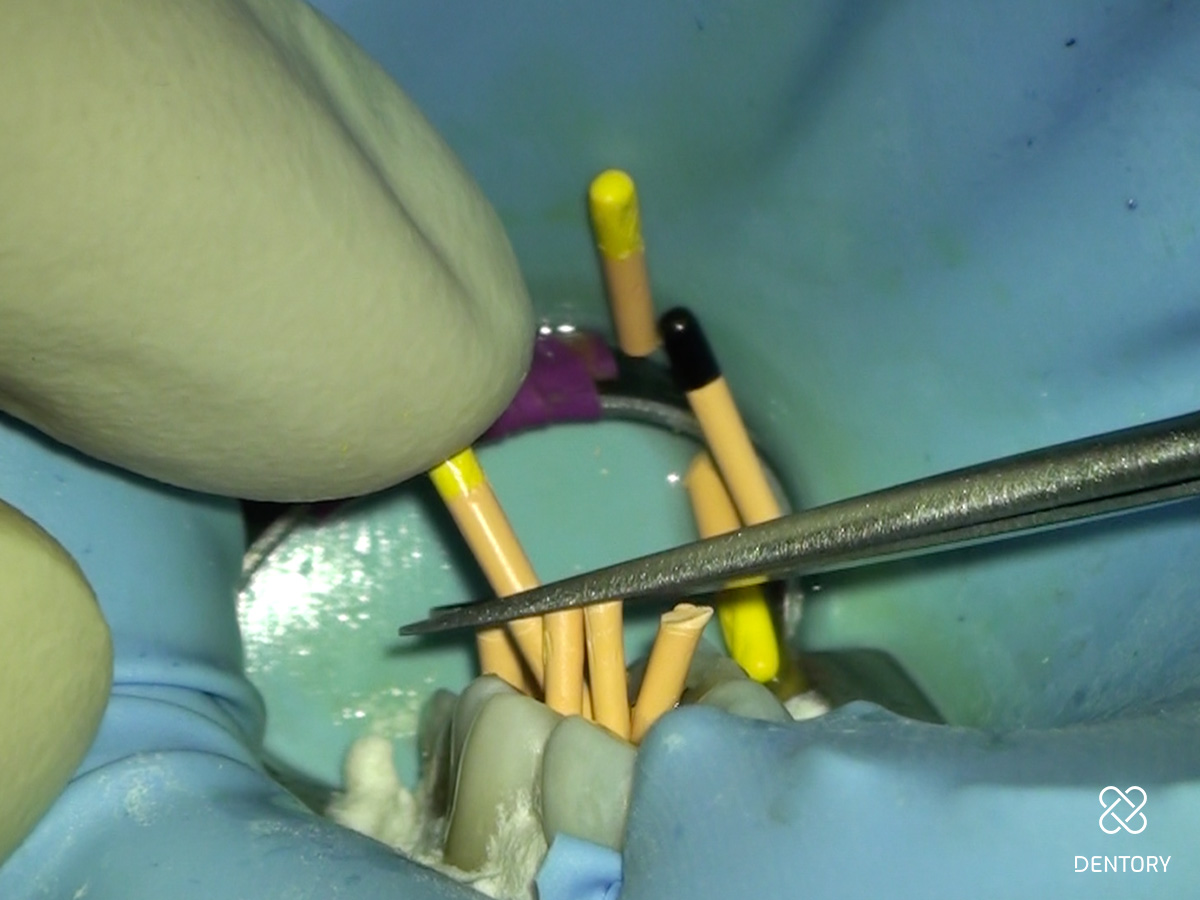

Abbildung 13

Einprobe der Guttapercha-Spitzen vor der Masterpoint-Aufnahme.